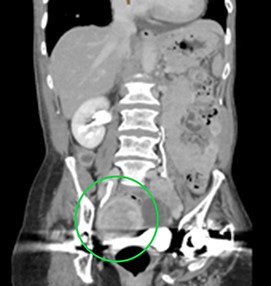

CT aortogram demonstrating a suspicious lesion arising from the right adnexa. Ultrasound confirmed a complex, vascular lesion arising from the right ovary and later biopsy proven as high-grade serous ovarian cancer.

The patient was admitted for further investigation. MRI brain demonstrated multiple sites of ischaemic change in both the anterior and posterior circulation (Fig. 2). A cardiac embolic source was considered and TTE demonstrated a small hypoechoic focus 6 mm ×3 mm on the aortic annulus reported as representing either thrombus or atheroma. Further serological testing ruled out autoimmune and inflammatory conditions. A CT aortogram + coronary angiogram to exclude dissection or coronary artery disease given the rise in troponin noted an incidental pelvic mass (Fig. 3) thought to be arising from the adnexa. A confirmatory pelvic ultrasound reported a lesion arising from the right ovary with complex and vascular structure. CA 125 was >1500 (normal ref < 100). The patient was transferred to a tertiary centre with specialist onco-gynaecological and general surgical services for biopsy, which confirmed stage III high-grade serous ovarian cancer.